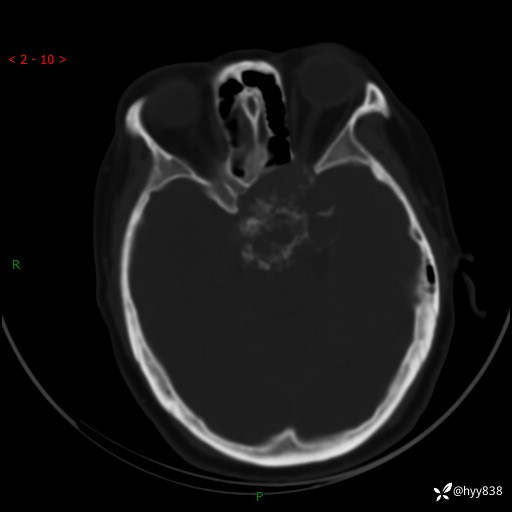

老年女性,视力下降3年。鞍区钙化性肿块,鉴别诊断有哪些---(有结果)

简要病史:患者3年前无明显诱因左眼出现视力下降,出现视物模糊,无头痛,无头晕,无恶心、呕吐,无意识障碍,无肢体麻木及抽搐,无心慌、胸闷,无腹痛、腹胀等不适,无旋地转感。个月前右眼视力下降,患者视物模糊逐渐下降,自诉看东西有雾感。在当地医院眼科就诊,症状无好转,行头部MR提示:鞍区肿物。现患者为求诊治来我科就诊,在当地市中医医院行头部CT:提示鞍区占位。患者现求进一步诊治来我院就诊,门诊以“鞍区肿物”收入我科。 患病以来,患者精神、饮食、睡眠尚欠佳,大小便如常,体力体重无明显变化。

临床诊断:鞍区肿物

颅脑CT平扫